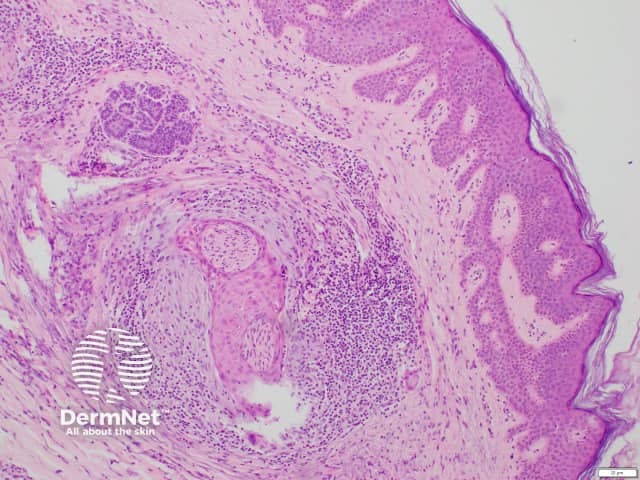

Epithelial sheath neuroma is diagnosed by histopathological examination of a skin biopsy. It is characterised by multiple enlarged peripheral nerve fibres that are sheathed by mature squamous epithelium. Epithelial sheath neuroma is sometimes surrounded by myxoid (mucus-like) stroma and a lymphocytic infiltrate.

Histology of epithelial sheath neuroma